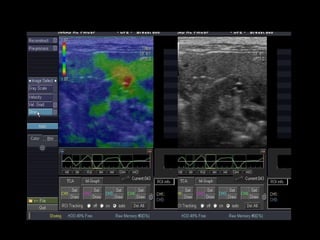

Modo B,  Modo Parametric Image (colorido) e gráfico Cm 2  Histogram . Neste exemplo, observa-se imagem no modo parametric image, áreas de fibrose (em vermelho e amarelo), que refletem a curva em azul no modo Cm histogram, de aspecto irregular, compatível com fibrose.